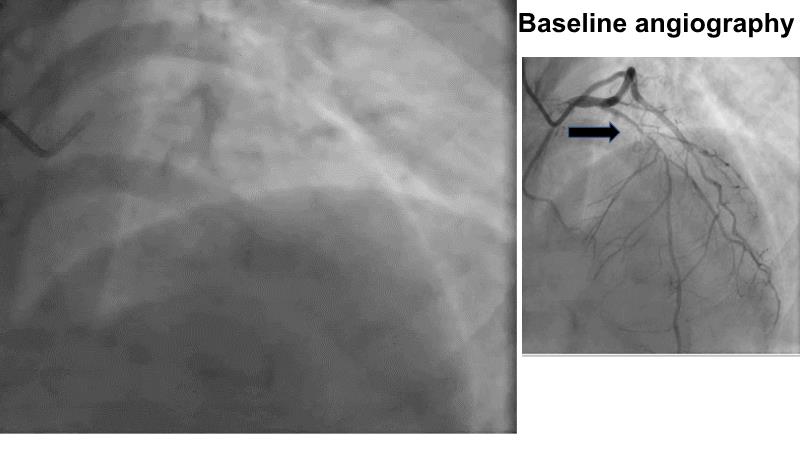

Calcified bifurcation lesion - LIVE case

Provisional stenting with Rotablator, IVL and IVUS-guided drug-eluting balloon

A 59-year-old female patient with type 2 DM, dyslipidaemia, hypothyroidism and impaired LV function (39%) presented with multivessel disease. RCA PCI was performed 3 days ago.

The prox and mid LAD showed a severe calcified lesion including the diagonal. The lesion was prepared using a 1.25 Rotaglide™ ('single-person' technique), followed by a 2.5 mm IVL.

The bifurcation was treated with an IVUS-guided stent (2.5 - 38 mm). This provisional stenting was completed by DEB kissing in the diagonal ostium and post-dilatation of the proximal LAD.